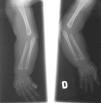

El EEG muestra una pobre estructuración del trazado de fondo, con múltiples descargas de punta-onda en ambas áreas temporales. En la serie esquelética destacan la reacción perióstica en huesos largos y una deformidad en copa de las metáfisis radiales (fig. 2). La densitometría ósea es normal. La RM y angiorresonancia cerebrales revelan un retraso de la mielinización, un infarto isquémico reciente en pálido derecho y unas arterias vertebrales elongadas y tortuosas (fig. 3).

Figura 2. Radiografía simple que muestra la reacción perióstica en huesos largos y una deformidad en copa de ambas metáfisis radiales.